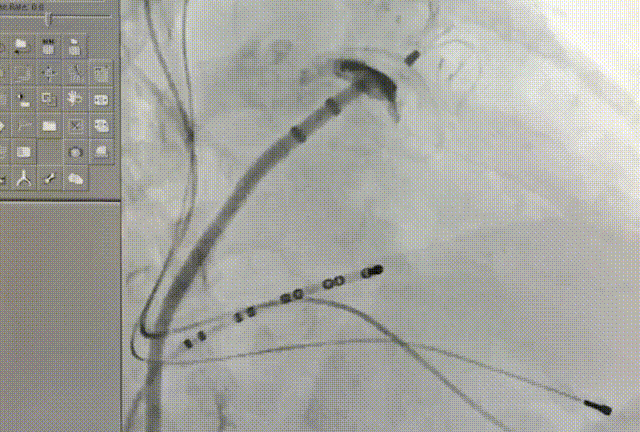

左心耳头位造影

左心耳测量

常规肝位造影显示,左心耳锚定区约26mm, 开口约29mm, 因此选择型号为LT-LAA-2834的LAmbre™左心耳封堵器对患者实施封堵。LAmbre™植入过程一步到位,U型钩均完全展开。随后复查造影及TEE结果,封堵盘呈“碗状”形态完美贴合于左心耳口部,无残余分流,牵拉测试稳定,综合评估符合COST原则,随后完美释放,封堵效果理想。术后,患者各项指标正常,身体恢复良好。